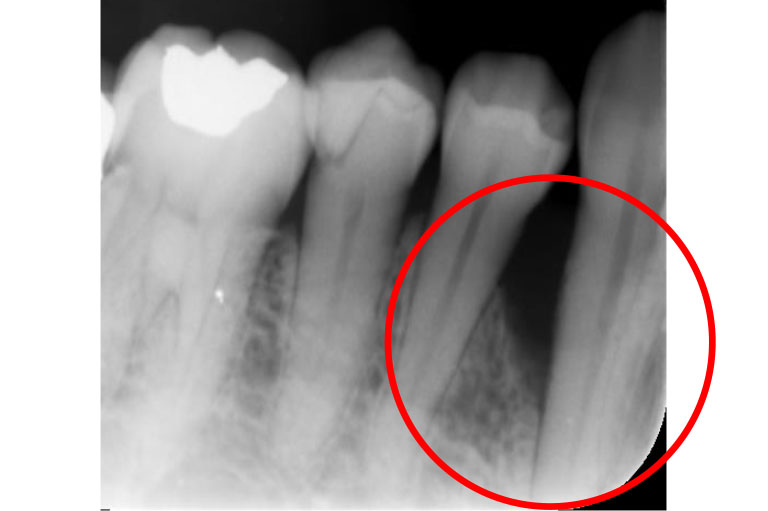

case.1

治療前

治療後

| 治療名 | 歯周組織再生療法 |

| 患者様情報 | 50代 女性 |

| 担当医 | 亀岡 聡貴 先生 |

| 費用 | 15.000円 (税込) 保険内 |

| 主訴 | 右下3番付近の歯茎が 1週間前から腫れている。 |

| 治療期間 | 1年 |

| 治療内容 | 歯周基本治療(SRP、TBI、咬合調整など)+歯周外科治療(再生療法)を行いました。全顎的に歯茎の炎症も落ち着き、レントゲン上でも骨の再生を認められました。 |

| 治療のリスク | 現在の状態の維持のため、継続的にメインテナンスを行う必要があります。 |